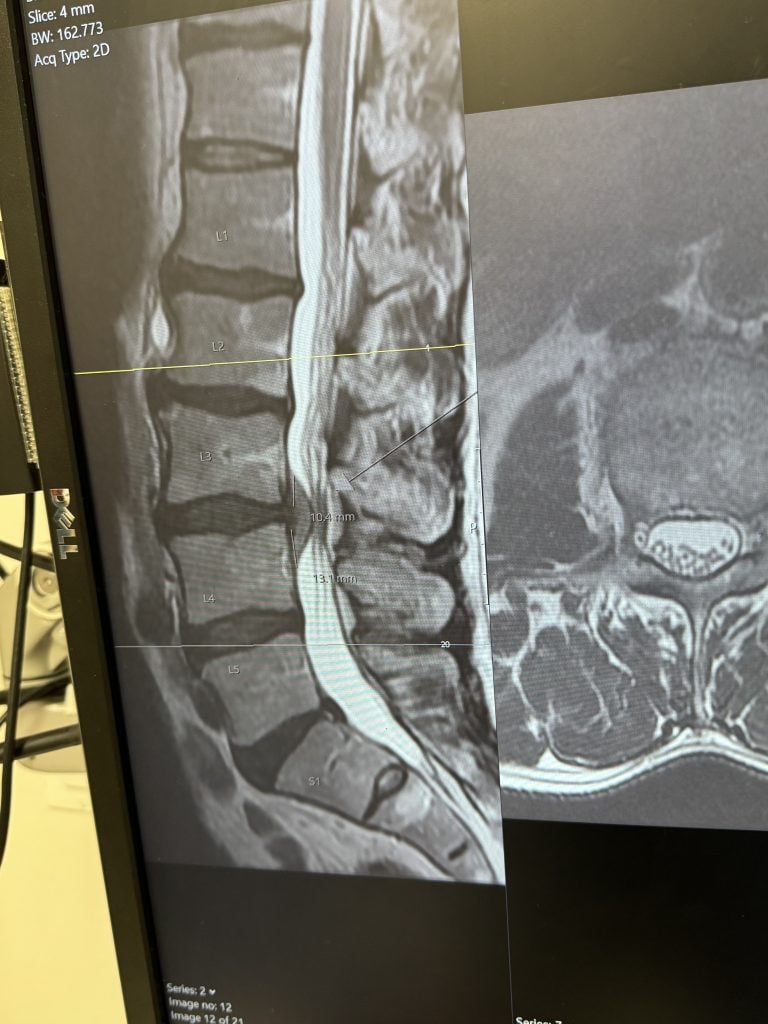

Microdiscectomy: Minimally Invasive Surgery for a Herniated Disc